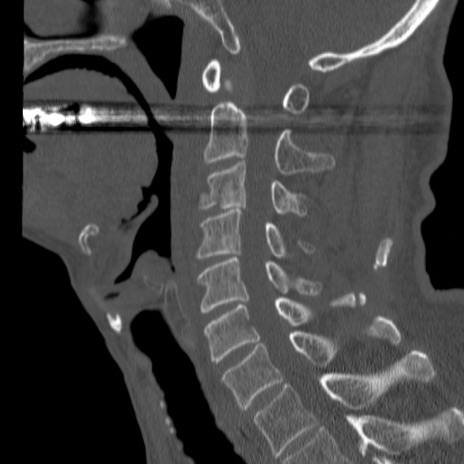

症例46 頚椎CT(矢状断像)

【症例】80歳代男性

【主訴】両側頚部〜上肢のしびれ

【現病歴】昨日、自宅内で転倒、その後より上記症状あり。意識障害なし。

【身体所見】両側上肢のallodynia(熱痛覚過敏)あり。MMTおよびDTRは正確な所見取れず。両上肢の挙上はなんとか可能。

異常所見と診断は?